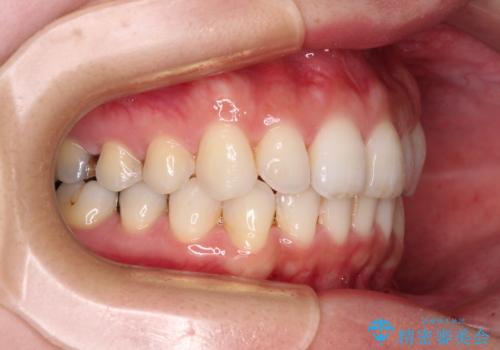

- 上下の前歯のデコボコを治したいとのことで来院された患者様です。

仕事柄、アジアの3つの国と地域を行き来するため、ワイヤー装置での治療は難しいと考えられました。

上下顎ともにIPR(歯と歯の間を削る)と歯列全体の拡大によって叢生が解消するように設計し、インビザラインにより治療を行うこととしました。